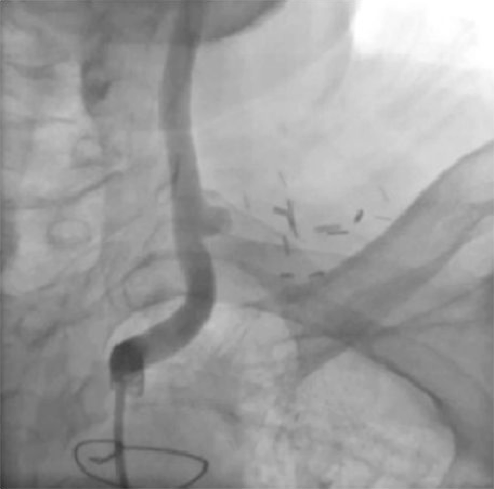

Figure 4B. Later in the left common carotid artery angiogram, filling of left subclavian from the vertebral artery is evident (click thumbnail to view larger image).

Upon transfer to our facility, a computed tomography angiogram (CTA) was performed, which revealed the bilaterally occluded bypass grafts and the ligated right SCA (Figure 2). Cardiac catheterization and angiography showed that both the proximal RCA and the left main were occluded. The SVG to RCA and OM1 were patent; SVG to D1 was occluded. The bilateral subclavian steals could be visualized with contrast injection into the bracheocephalic and left common carotid arteries (Figures 3 and 4). The LIMA was faintly visualized during the late filling phase of the left carotid angiogram (Figure 4); the left SCA and LIMA filled via collaterals from the left vertebral artery.